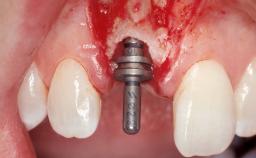

Late Flapless Placement of an Implant in a Maxillary Left Central Incisor Site

A 39-year-old male patient presented with a chief complaint of discomfort and gingival discoloration around his maxillary left central incisor. He was in good general health and was a non-smoker. His past dental history was significant because of the traumatic fracture of tooth 21 in a sporting accident at age 13. Initial dental treatment included endodontic therapy and a full-coverage restoration. The patient became symptomatic 5 years later, when structural failure of the tooth resulted in the dislodgment of the crown. Endodontic retreatment, apical surgery, and post-and-core restoration were performed.

Type of Implants One-Piece

Attachment One-Piece

Bone Volume Deficient horizontally, requiring prior grafting